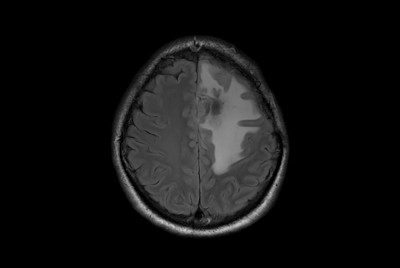

SmartSpeed Precise imaging for brain with glioblastoma

Pediatric Brain imaging for glioma

Alzheimer’s Disease Anti-Amyloid Immunotherapies (ARIA) 3.0T

Large lesion brain imaging with synthetic MRI

Brain with glioblastoma

Brain glioblastoma, post-operative